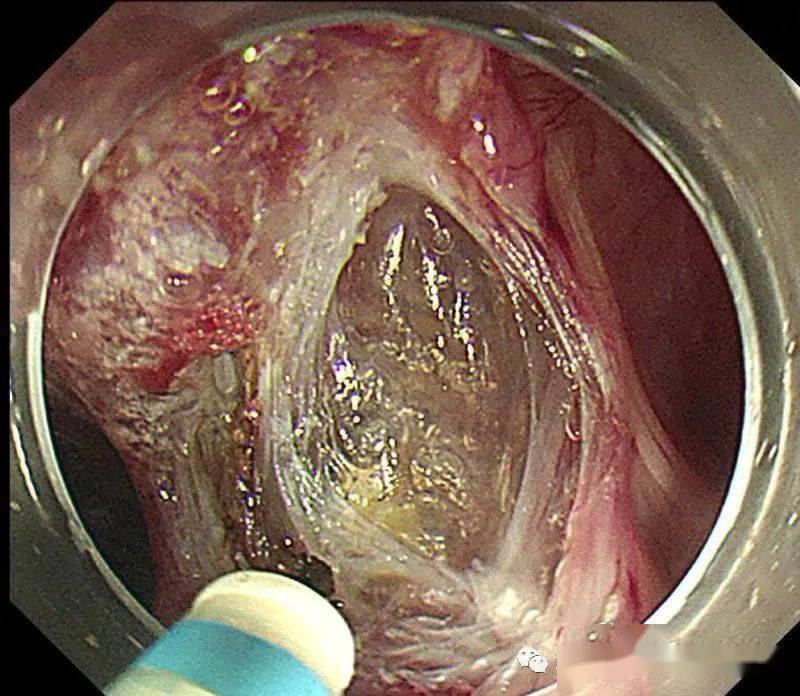

巧破堤坝治疗食管憩室

为实现食管的生理修复和功能重建,解放军总医院消化内科医学团队开创